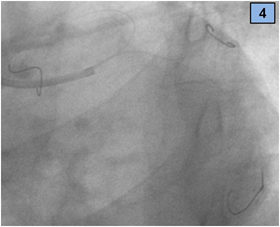

A seven French extra back-up catheter was placed in the ostium of the left coronary artery. Three guidewires were advanced: one in the LAD artery and the other two in the CX artery and branches. While crossing the CX occlusion with the wire, the vessel opened spontaneously (Figure 4) and an image suggestive of thrombotic material was seen in the CX and the second obtuse marginal branch (Figure 5).

Figure 4 Three wires were placed, one in LAD and two in CX (marginal branches).